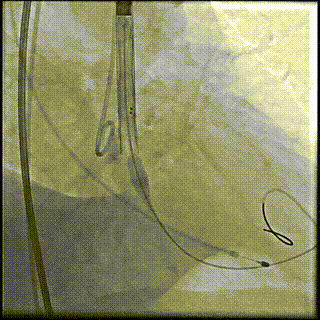

第一次释放到工作位

工作位造影位置偏深

完全回收再次定位

第二次释放到工作位,位置理想

瓣膜完全释放

瓣膜完全释放后造影